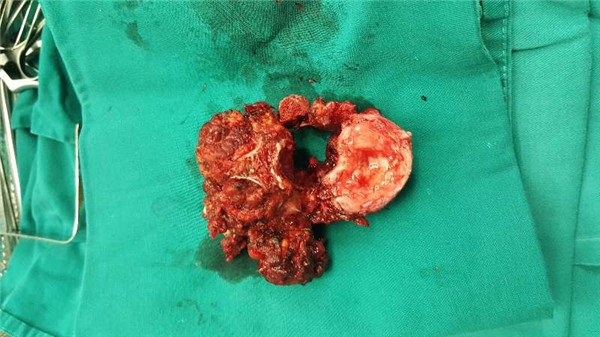

术中 椎体切除